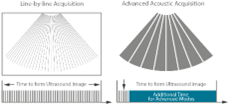

Advanced Acoustic Acquisition

Πρωτοποριακή τεχνική σάρωσης σε ζώνες προσφέρει πολλαπλάσια ταχύτητα λήψης και επεξεργασίας σε σχέση με συμβατικούς υπερηχογράφους.

Πρωτοποριακή τεχνική σάρωσης σε ζώνες προσφέρει πολλαπλάσια ταχύτητα λήψης και επεξεργασίας σε σχέση με συμβατικούς υπερηχογράφους.

Με τη μετάδοση και λήψη σχετικά μικρού αριθμού μεγάλων ζωνών, η τεχνολογία Advanced Acoustic Acquisition εξάγει περισσότερες πληροφορίες από κάθε δέσμη, 10 φορές πιο γρήγορα από ό, τι μια συμβατική μέθοδο συλλογής γραμμή προς γραμμή.

Dynamic Pixel Focusing

Η τεχνολογία αυτή δίνει την δυνατότητα στο Consona N8 για την επίτευξη πλήρης ομοιομορφίας σε επίπεδο pixel σε όλη την εικόνα. Ως εκ τούτου, δεν υπάρχει πλέον η ανάγκη συνεχόμενης προσαρμογής των εστιακών θέσεων για την επίτευξη καθαρότητας στην εικόνα κατά την εξέταση του ασθενούς.

Η τεχνολογία αυτή δίνει την δυνατότητα στο Consona N8 για την επίτευξη πλήρης ομοιομορφίας σε επίπεδο pixel σε όλη την εικόνα. Ως εκ τούτου, δεν υπάρχει πλέον η ανάγκη συνεχόμενης προσαρμογής των εστιακών θέσεων για την επίτευξη καθαρότητας στην εικόνα κατά την εξέταση του ασθενούς.